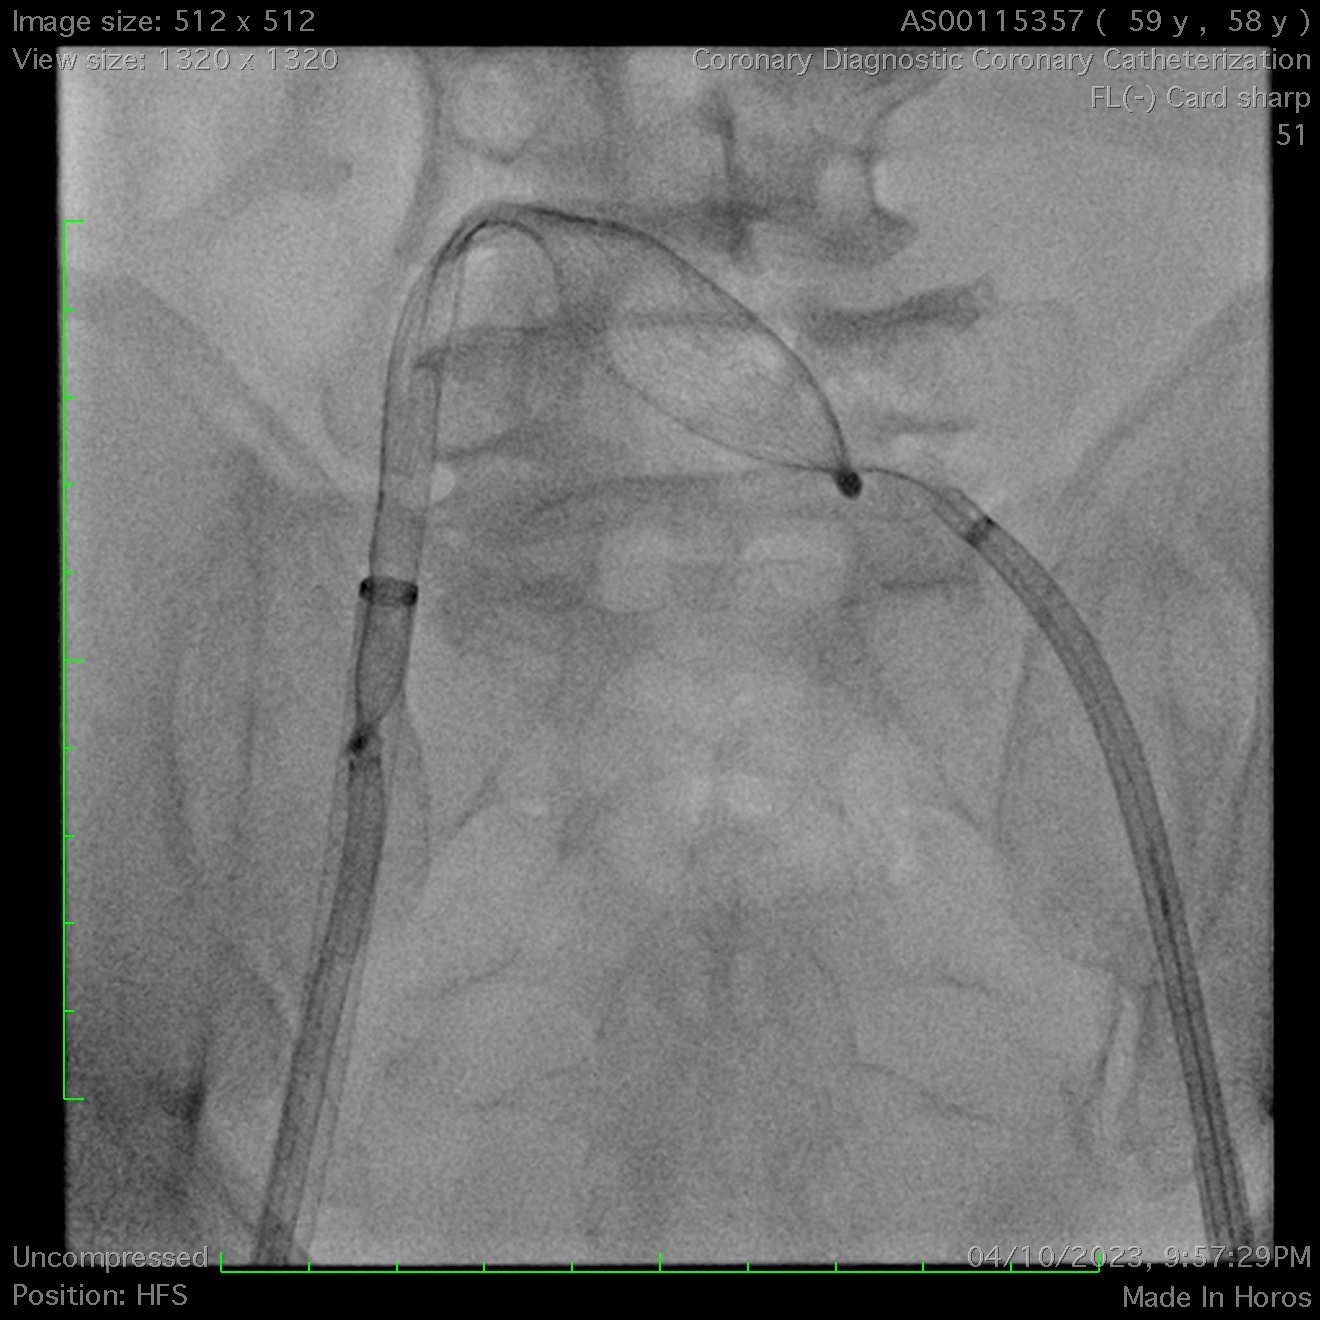

A 36mm ASD occluder was successfully deployed after confirming optimal position & stability. Unfortunately, post-release, the device embolized into the right ventricle. Agilis steerable catheters were inserted to bilateral femoral veins. Initial attempts to snare the occluder's hub with a single-loop snare proved challenging due to its high mobility within the right ventricle, even when stabilized with a steerable mapping catheter. A modified snare with a larger loop, made from a guiding catheter, coronary wire, and balloon, was employed but failed to capture the hub after multiple attempts.

Ultimately, a biopsy forceps was used to grasp the atrial disc and pull it into the inferior vena cava. This stabilized the occluder, enabling successful snaring of the left atrial disc’s hub into the left femoral sheath. Subsequently, a second snare was deployed from the right femoral sheath to capture the right atrial disc’s hub, allowing its sheathing & subsequent removal.